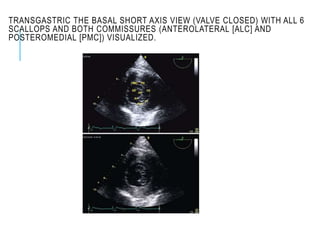

TRANSGASTRIC THE BASAL SHORT AXIS VIEW (VALVE CLOSED) WITH ALL 6

SCALLOPS AND BOTH COMMISSURES (ANTEROLATERAL [ALC] AND

POSTEROMEDIAL [PMC]) VISUALIZED.

TRANSGASTRIC THE BASAL SHORT AXIS VIEW

(VALVE OPEN) WITH ALL 6 SCALLOPS

VISUALIZED